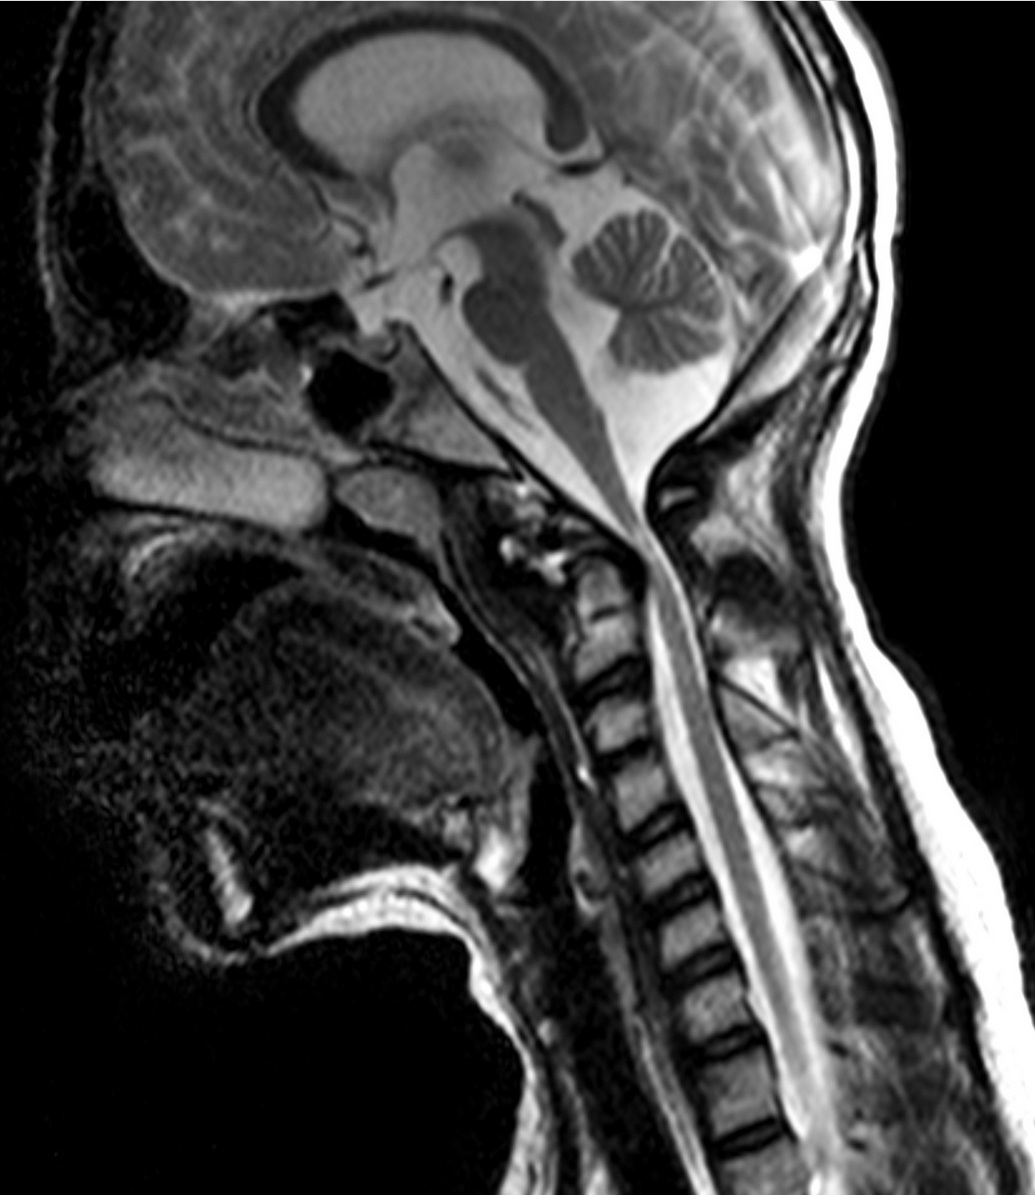

HNP (hernia del núcleo pulposo)

Dolor de espalda, radicular, ciática déficit neurológico asociado a compresión de raíz.

Evaluación de compresión cervicomedular y decisión de descompresión posterior.

Correlación clínico-radiológica y decisión de descompresión según síntomas y hallazgos.